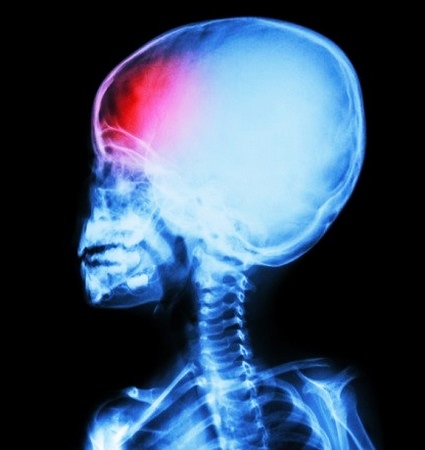

Отдельно различают гипоксию плода, которая иногда наблюдается во время беременности. Патология опасна в любом триместре, потому что не позволяет эмбриону, а в дальнейшем и плоду нормально развиваться. Если мозг плода в течение длительного времени испытывает дефицит кислорода, то в его крови начинает скапливаться углекислота.

В ряде случаев именно из-за гипоксии ребенок рождается недоношенным (роды проводятся через кесарево сечение, т.к. рождение обычным способом противопоказано). Новорожденный младенец, если он страдал от гипоксии в утробе матери, с высокой долей вероятности столкнется в дальнейшем с различными неврологическими нарушениями.